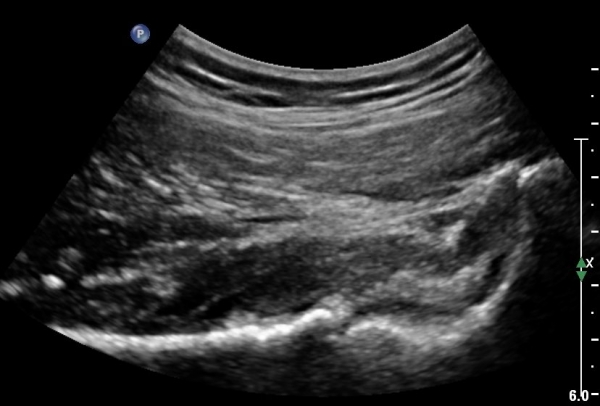

°í°üÀý ¿ÜÃø, ¹Ù·Î µÚ Á¾´Ü¸é°Ë»ç¿Í Ⱦ´Ü¸é °Ë»ç»ó °üÀý ¿Í¼øºÎÀ§¿¡ Ä¿´Ù¶õ °í¿¡ÄÚ ¼®È¸È­°¡ °üÂûµÊ(»çÁø 8, 9)